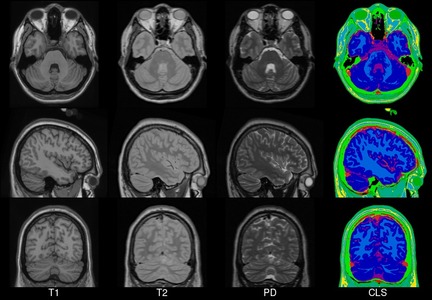

Transverse, sagittal and coronal views of four generations (all T1-weighted images) of MNI space template from left to right. Note that MNI52 has greater z-axis coverage than MNI305 and that the 40th-generation non-linear MNI152 combines the detail apparent in the single subject Colin27 template with the group representativeness of MNI305 or MNI152.

MNI152

In 2001, within the ICBM project (Mazziotta et al., 1995, 2001a,b), three sites (MNI, UCLA, UTHSCSA) each collected ~150 MRI volume images from a normative young adult population. These images were acquired at a higher resolution than the MNI305 data and exhibited improved contrast. To create MNI152 (a.k.a. ICBM152), each individual in the MNI cohort was linearly registered to MNI305. This new template exhibits better contrast and better definition of the top of the brain and the bottom of the cerebellum due to the increased coverage during acquisition. An automated analysis pipeline (Zijdenbos et al., 2002) also generated gray/white/CSF maps. The templates for image intensity (T1, T2,PD) and tissue type (GM, WM, CSF) maps have subsequently been incorporated into other popular brain mapping software, e.g. SPM, FSL AIR, LORETA,VARETA, BRAINWAVE. In 1996, regional probability maps were generated from the MNI152 database. The MRI volume from a single subject (“Jacob”) was manually segmented into 142 sub-regions. Each subject’s MRI was non-linearly registered to the Jacob atlas using ANIMAL (Collins et al., 1995, 1999), such that the atlas labels were transferred to each of the individual MRI data volumes. These labels were then linearly mapped to MNI152 space to generate regional probability maps.